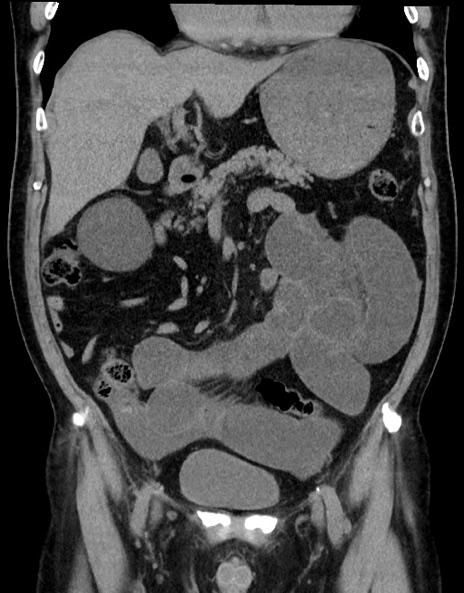

症例15(冠状断像)

【症例】70歳代男性

【主訴】腹痛

【現病歴】今朝から腹痛あり。全体的に痛い。特に左上の方。排ガスが今日はない。冷や汗が出る。

【既往歴】直腸癌術後

【身体所見】左側腹部〜上腹部に圧痛あり。腹膜刺激症状明らかなではない。軽度反跳痛。左下腹部に術後瘢痕あり。

【データ】WBC 7700、CRP 0.02